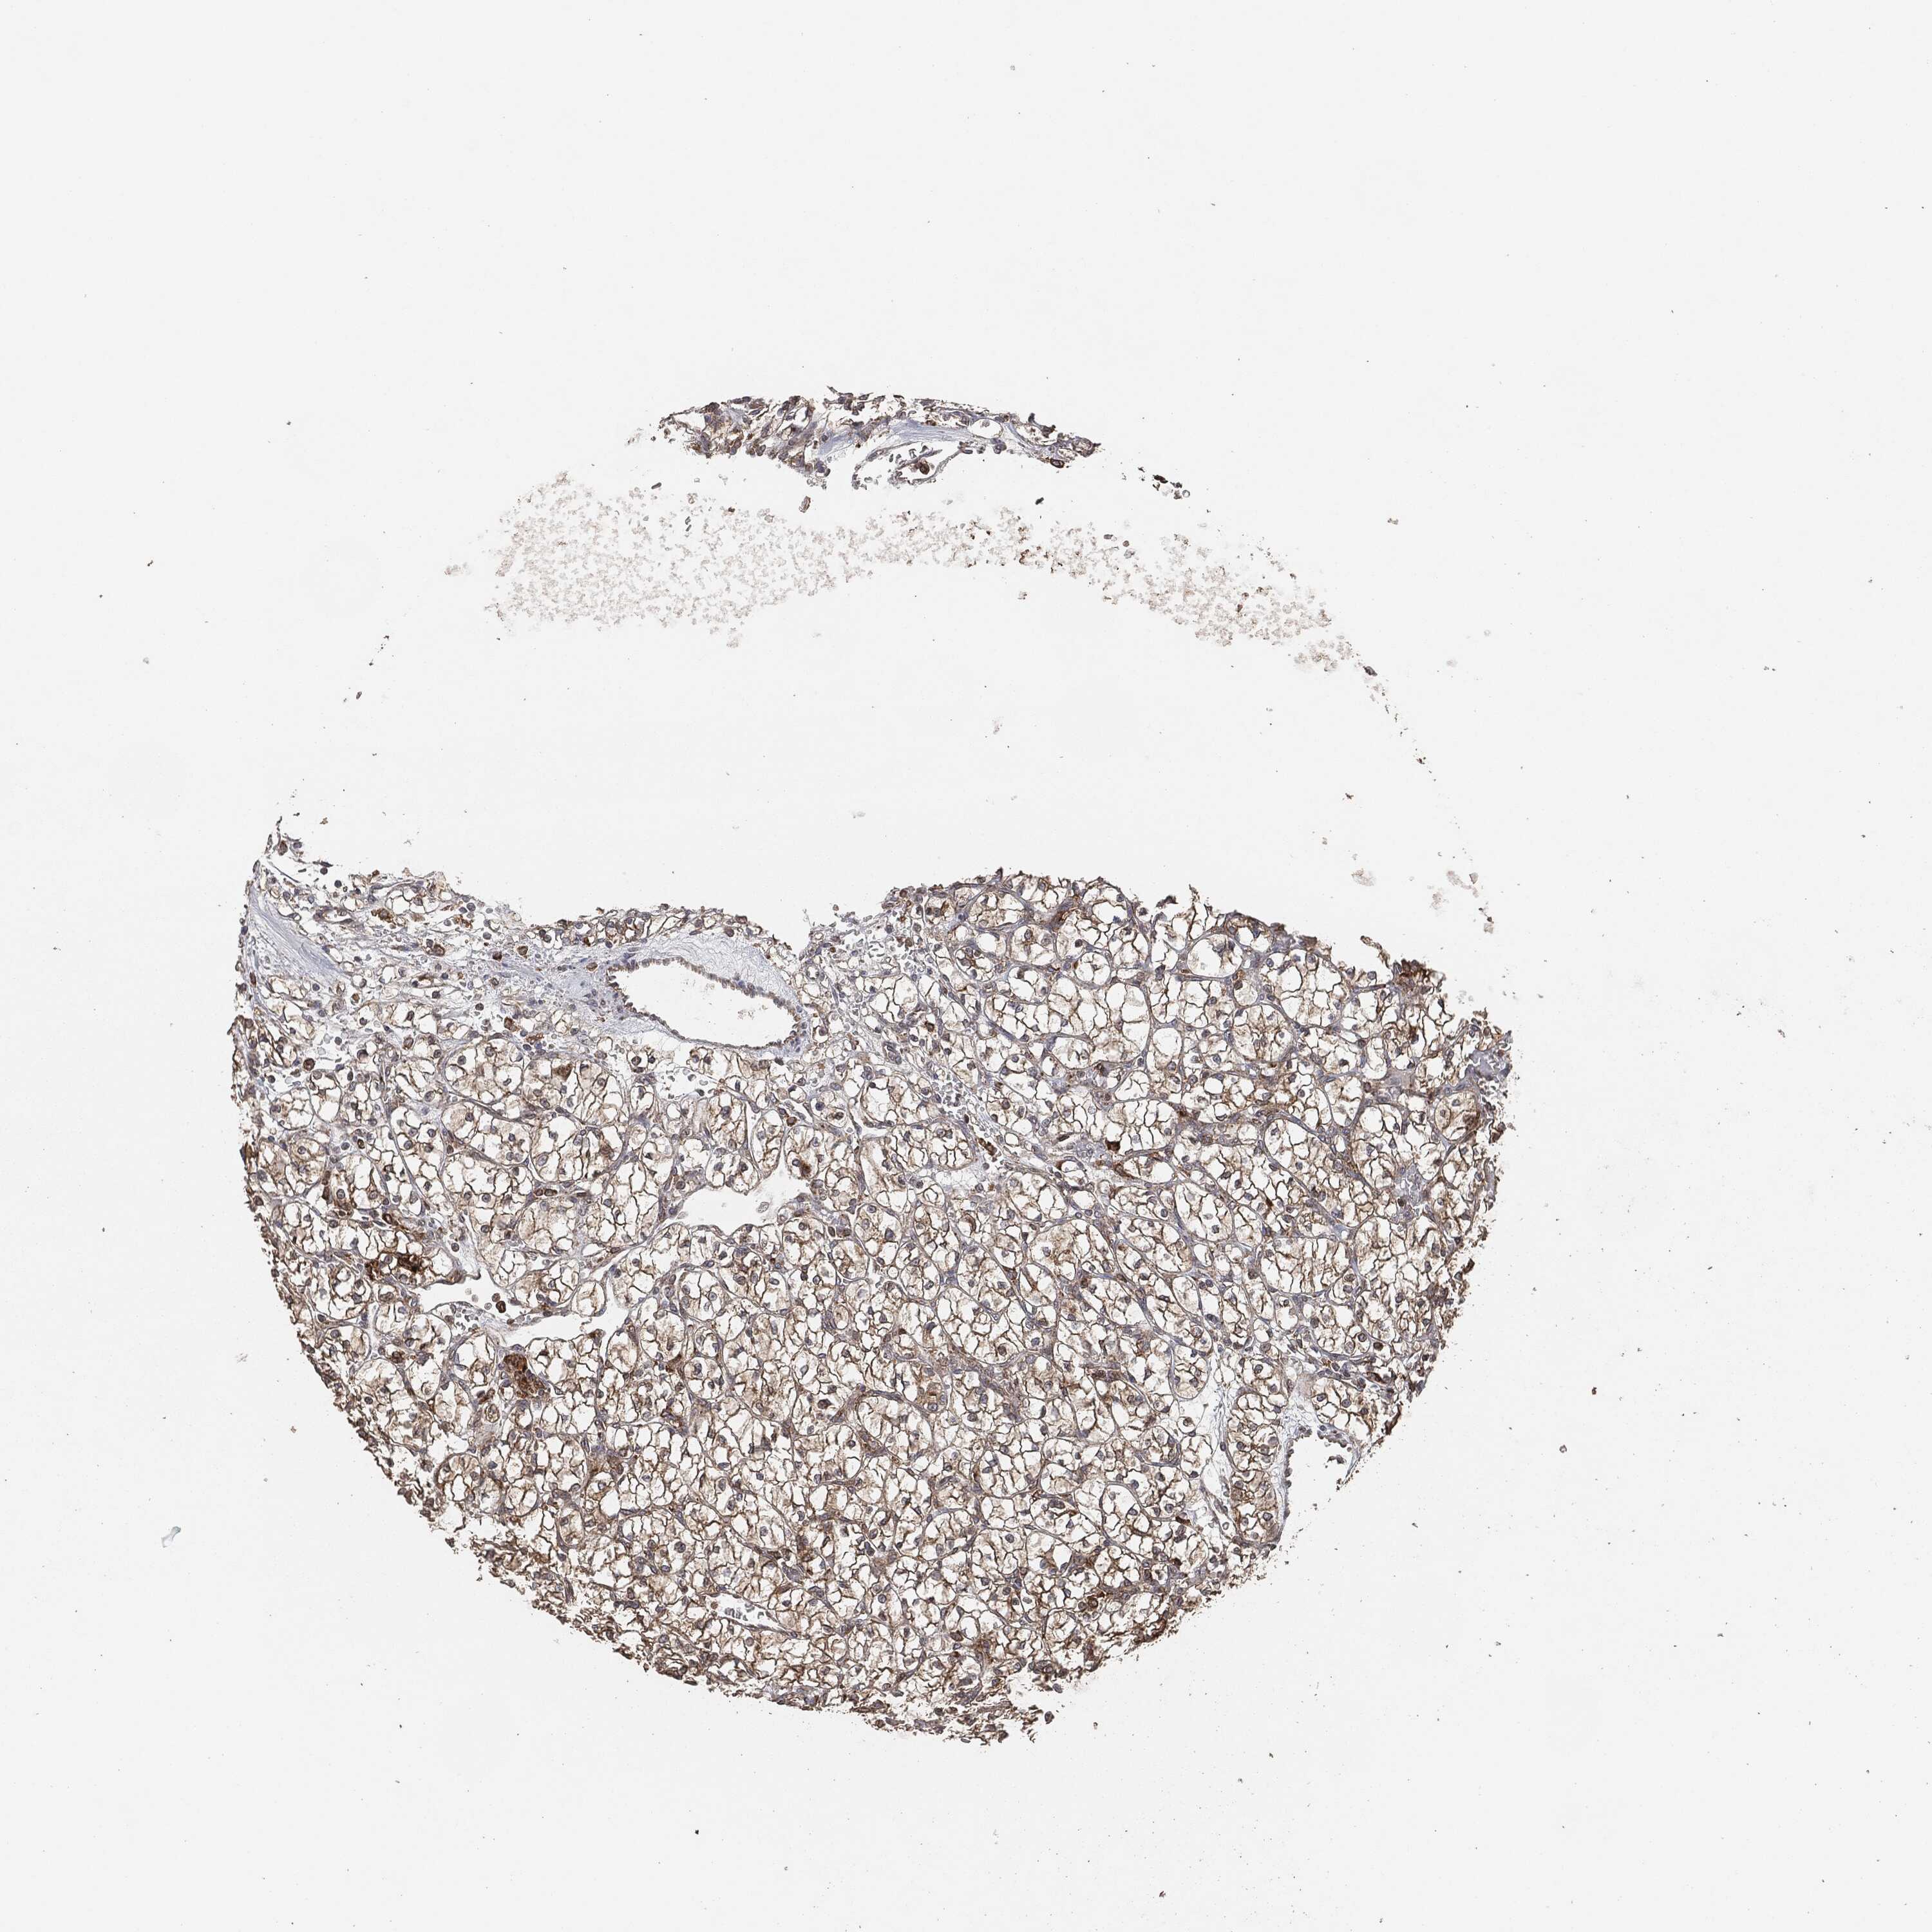

CANCER RENAL CANCER Show tissue menu

KICH TCGA KIRC TCGA KIRC VALIDATION KIRP TCGA PROTEIN RCC CPTAC PROTEIN EXPRESSION